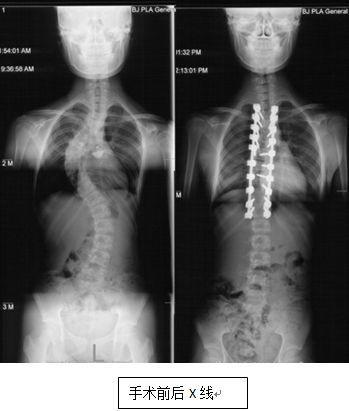

脊柱侧弯,顾名思义,就是脊柱在X光片上呈现侧弯的形态。这种疾病在成年人中并不少见,据统计,我国成年人脊柱侧弯的发病率约为2%-3%。脊柱侧弯不仅会影响外观,还会导致腰背疼痛、活动受限等问题。